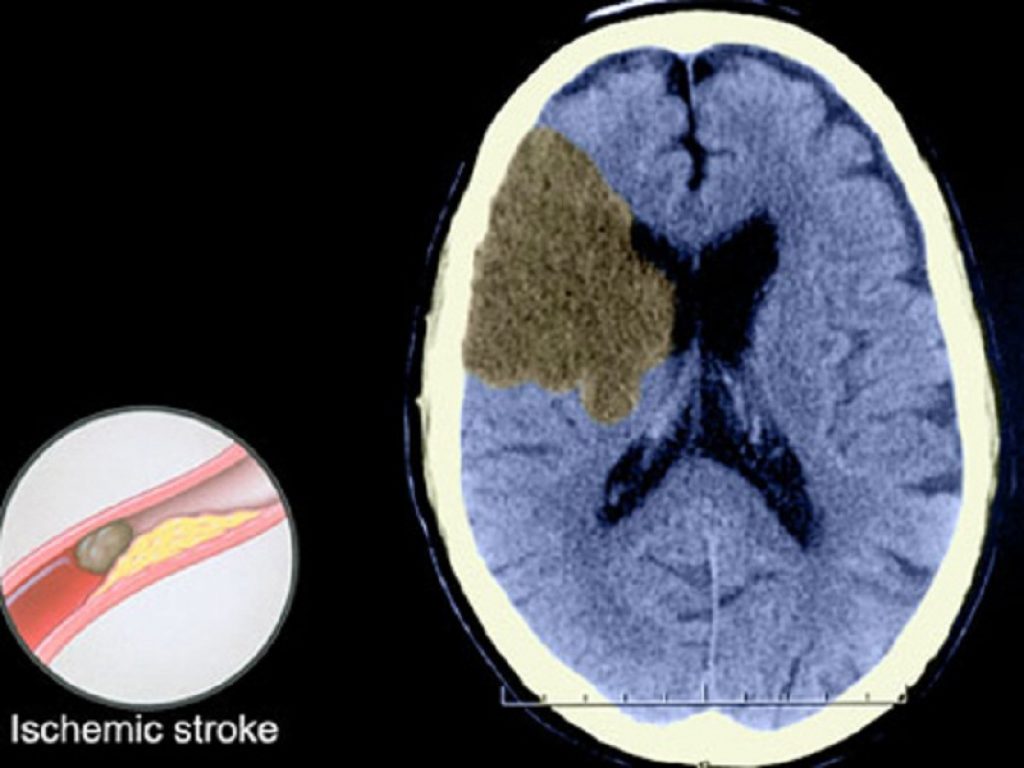

Uno studio di notevole rilevanza clinica, pubblicato su “JAMA Neurology”, suggerisce che i pazienti colti da ictus ischemico con occlusione dei grandi vasi circolatori anteriori che si presentano molto tardi all’accettazione – da >16 ore a 10 giorni dal momento in cui erano riconosciuto bene (LKW) – possono trarre beneficio dal trattamento endovascolare (EVT).

«L’importanza dello studio» spiegano gli autori, guidati da Beom Joon Kim, dell’Ospedale Universitario Nationale Bundang di Seul (Corea del Sud) «sta ne fatto che l’EVT dopo ictus ischemico dovuto all’occlusione emergente di grandi vasi è solitamente limitato da una finestra specifica inferiore a 16-24 ore dall’ultima volta che il paziente è stato identificato (LKW), mentre i pazienti con progressione lenta e circolazione collaterale tenace possono persistere oltre le 16 ore».